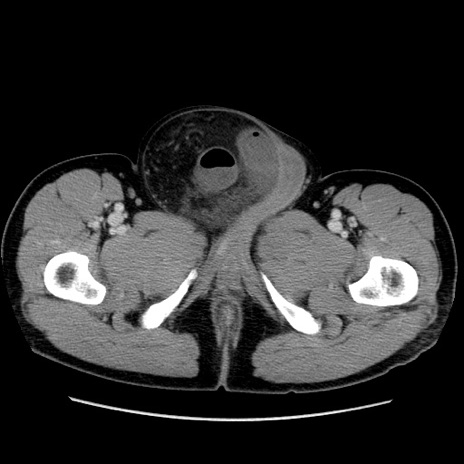

症例34(横断像)

【症例】60歳代 男性

【主訴】右鼠径部膨隆

【現病歴】1年程前より右鼠径部膨隆あり。自己にて還納可能だったため放置していた。3時間前より右鼠径部の脱出を認め、還納困難となり受診。

【身体所見】右鼠径部に小児頭大の膨隆あり。弾性硬であり、用手還納は困難。左鼠径部にも膨隆を認める。脱出はなし。